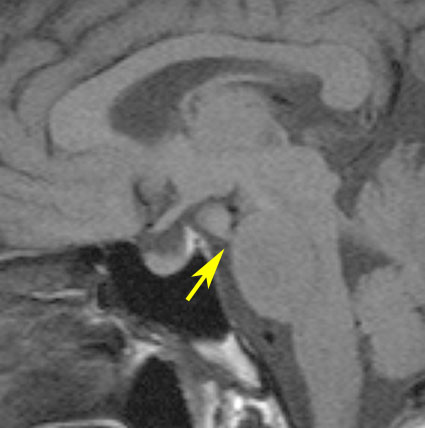

無症候で発見されたpedunculated typeです。視床下部の底面からぶら下がるようにしてあります。左のCISS画像で形がよくわかります。中央のT1では灰白質と等信号です。右のT2では高信号となっています。

乳頭体(矢印)からは離れているタイプです。ですから笑い発作を生じません。右側のガドリニウム増強画像ではまったく増強されていないのが特徴です。